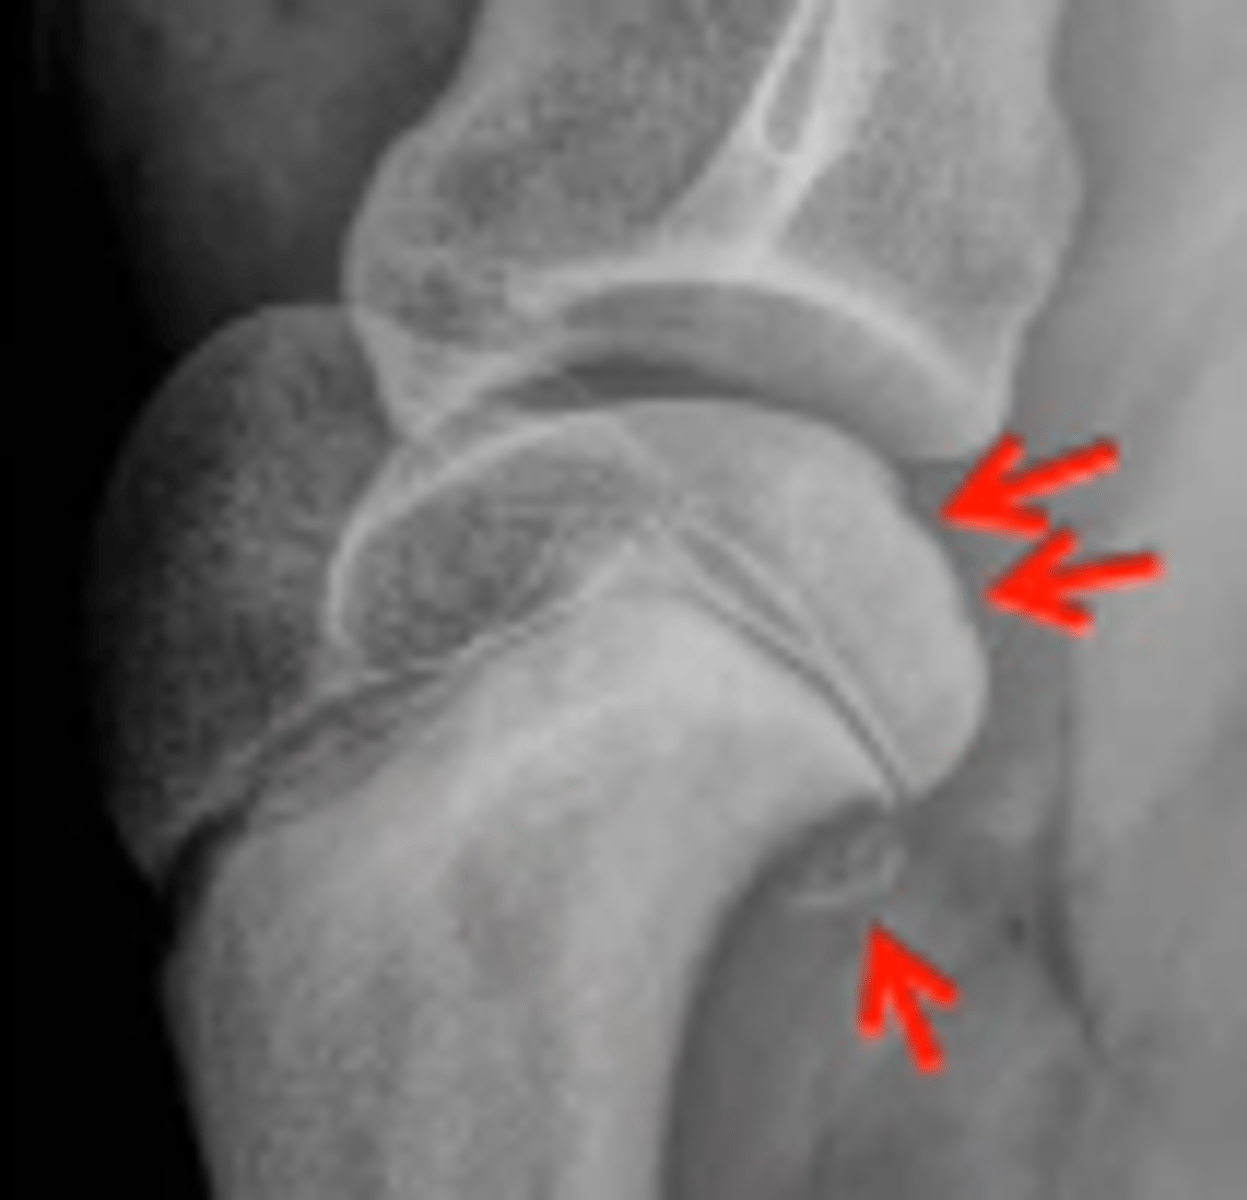

Osteochondrosis

-Red arrows show disc like depressions

What will osteochondrosis (developmental) present as?

Loss of rounded contour of caudal surface of humeral head

Radiolucent defect

May have surrounding sclerosis

May have calcified free body in joint